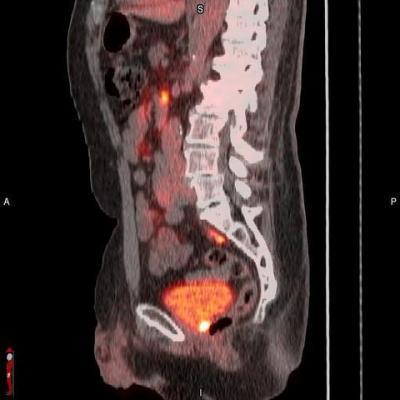

POSLUMA (flotufolastat F 18) PET/CT image showing uptake in the prostate bed, consistent with recurrent prostate cancer Photo courtesy of Blue Earth Diagnostics

September 27, 2023 — Blue Earth Diagnostics, a Bracco company and recognized leader in the development and commercialization of innovative PET radiopharmaceuticals, announced presentations on POSLUMA (flotufolastat F 18) injection (formerly known as 18F-rhPSMA-7.3) at the upcoming American Society for Therapeutic Radiology and Oncology (ASTRO) 2023 Annual Meeting, to be held in San Diego, Calif., from October 1 to 4, 2023. POSLUMA is indicated for positron emission tomography (PET) of prostate-specific membrane antigen (PSMA) positive lesions in men with prostate cancer with suspected metastasis who are candidates for initial definitive therapy or with suspected recurrence based on elevated serum prostate-specific antigen (PSA) level.